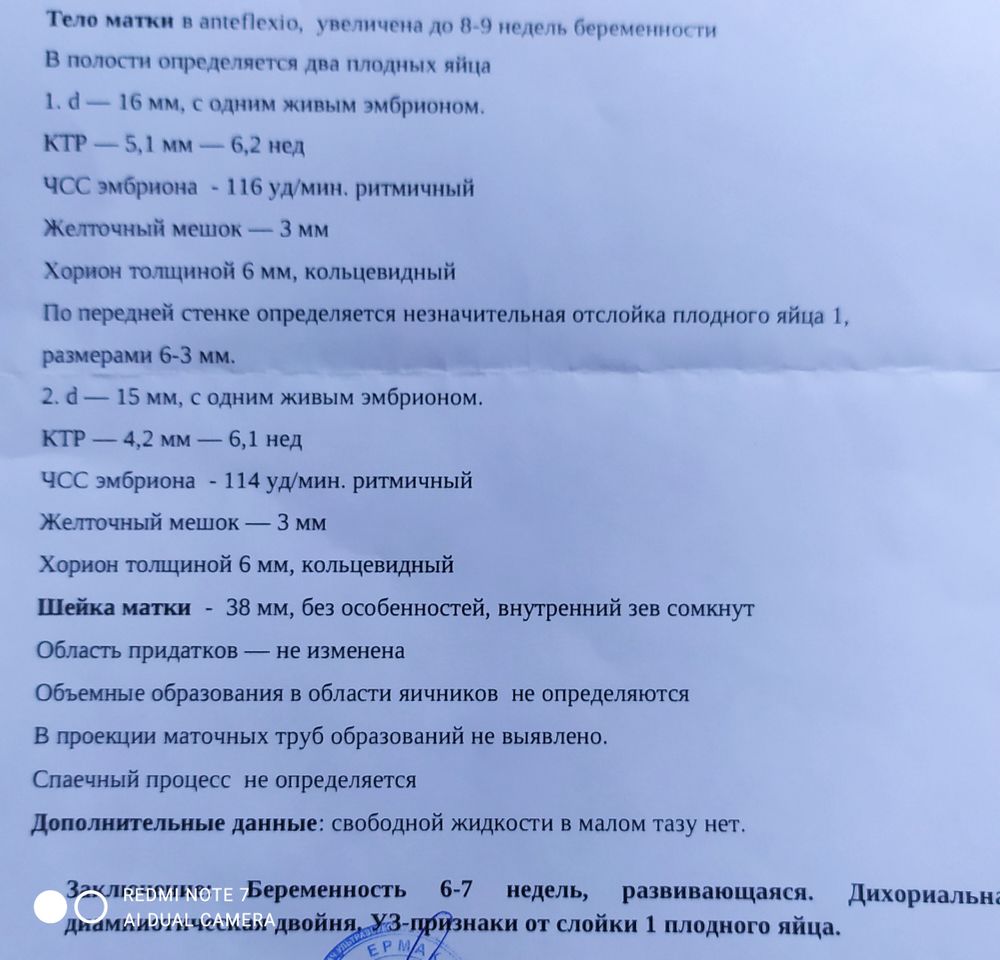

Сходила сегодня на УЗИ.

Всë в норме, 2 плодовых яйца!!!